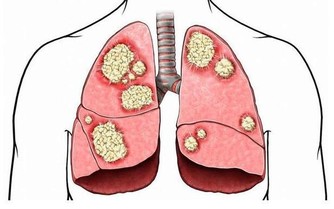

長期體內不間斷的惡性循環,久而久之就會導致致癌物在體內累積,引發各種癌症。

糞便留在腸道內,有害物質被再次吸收,可引起胃腸神經功能紊亂而致食欲不振、腸胃不適、腹部脹滿、口苦、肛門排氣多等表現,甚至可誘發結腸癌。